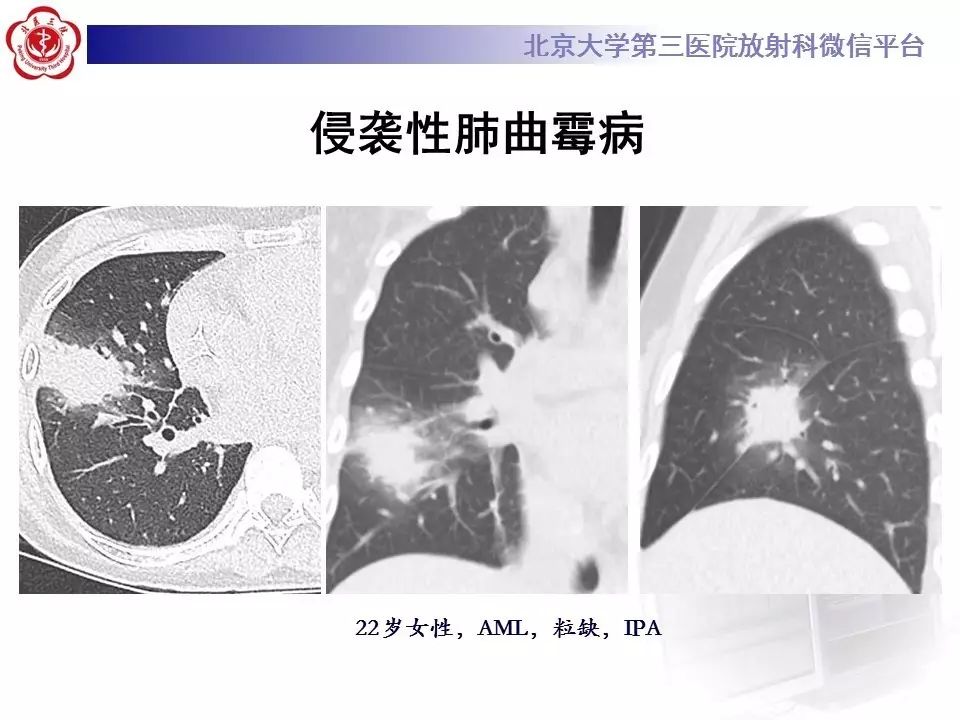

作者:朱巧、王晓华

本文转发自北京大学第三医院放射科